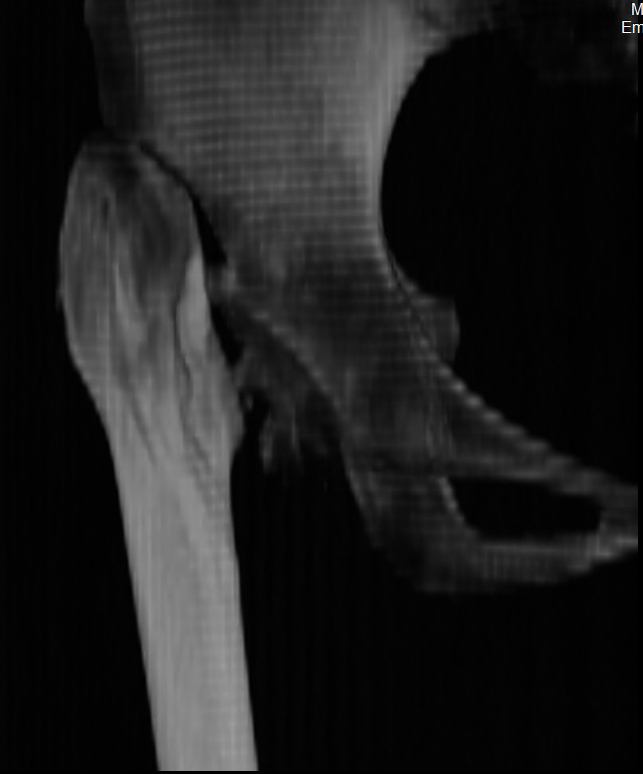

Сделал ей КТ.

С удивлением узнала, что перелом в области шейки у неё не сросся, хотя на рентгенограмме тех лет так оно и есть.

КТ - во вложении.

Интересна функциональная адаптация - практически полная функция того, что раньше было тазобедренным суставом.

>К нам обратилась пациентка 29 лет. В 9 летнем возрасте, падение с

>качелей. Перелом правого бедра: диафиза и шейки. Рентгенограмм нет, но

>судя по рассказам пациентки, перелом шейки бедра нашли через два месяца

>консервативного лечения перелома диафиза. Через 2 месяца после травмы

>оперативное лечение перелома диафиза накостным остеосинтезом, шейку

>лечили консервативно.